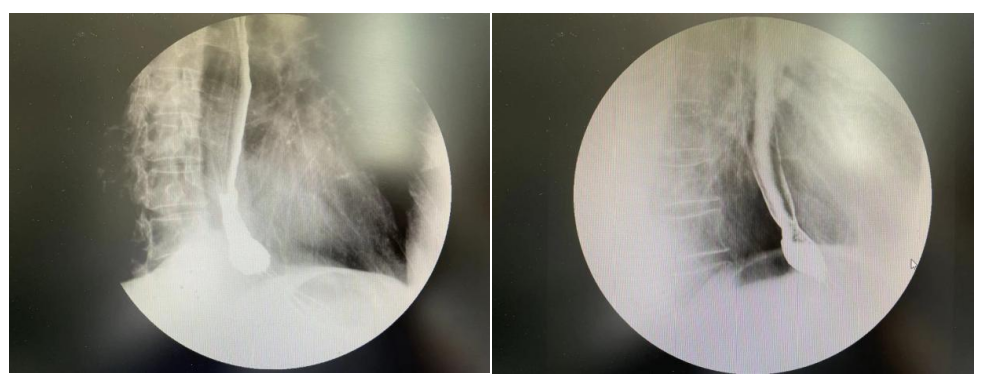

因患者有严重的慢性肺阻塞性疾病,计划优化过程中尽量降低双肺低剂量受照体积。放疗期间予以奥沙利铂+替吉奥双药同步放化疗。治疗期间出现II度骨髓抑制,I度消化道反应,治疗过程中吞咽困难逐步改善,放疗结束后进食梗阻症状完全消失。

放疗前,放疗后食管钡餐造影对比图像